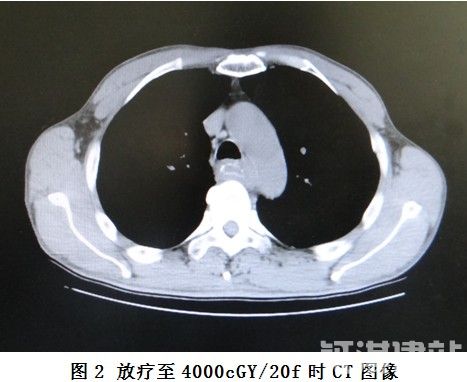

放疗6次时,患者体温逐渐下降,9次时发热症状消失,进食哽咽症状有所缓解。放疗至20次时复查食管CT(见图2)与放疗前定位CT片(见图1)比较,肿瘤明显缩小。放疗至DT6600cGY/33f时,进食哽咽症状明显缓解,复查食管CT(图3),见肿瘤进一步缩小。期间复查肝、胆、胰、脾、腹腔淋巴结、浅表淋巴结彩超未见明显异常。